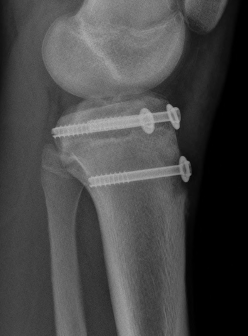

Type IV

Pace et al J Pediatr Orthop 2013

- 23 Type IV treated with surgery

- ORIF with screws

- 4 patients required supplemental plate fixation

- 1 compartment syndrome, 1 DVT

- 100% union

- no growth disturbances